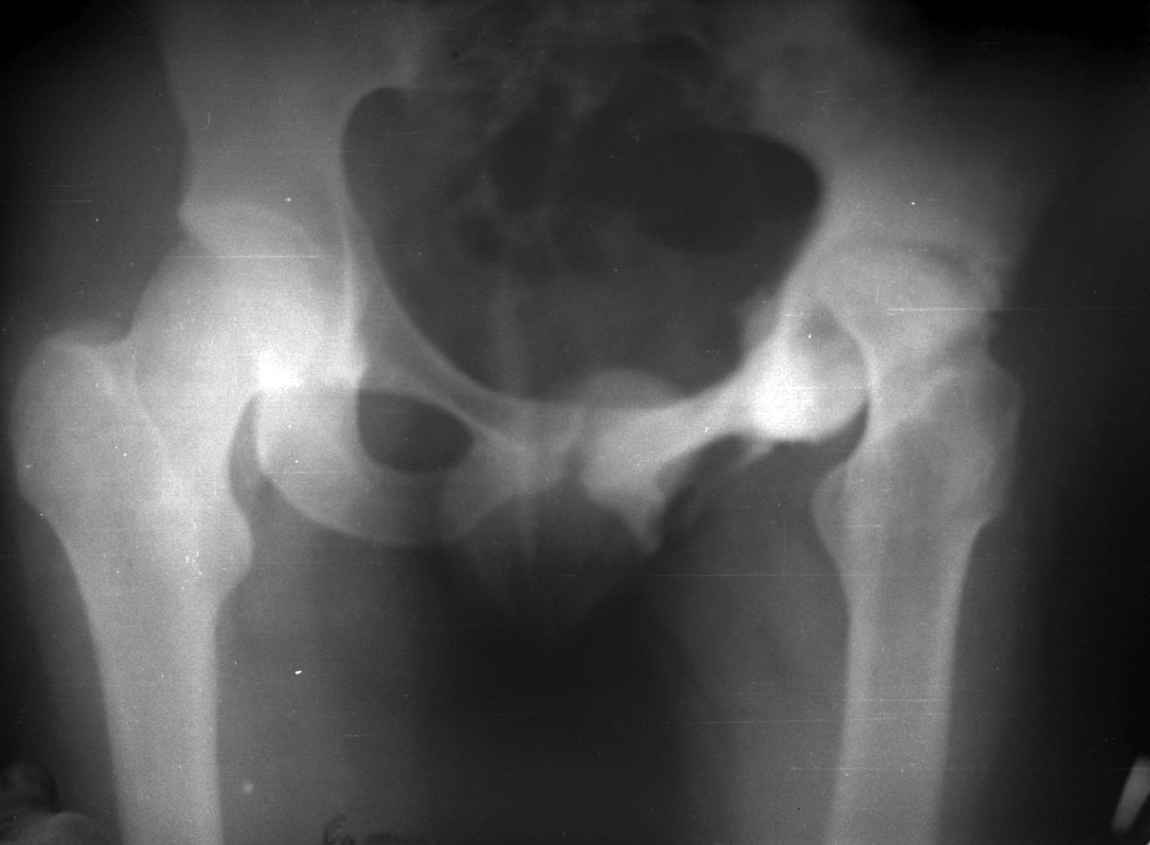

остеотомии. Я представил Р-граммы больных с неудачными р-ми после остеотомий.

Эндопротезирование у них было на порядок сложнее в отличие от артропластики без проведения остеотомии.

.........наверное не повезло. Но иногда это выход и очень хороший. М., 21 года спрыгнул в Армии с машины с исходом в гнойный коксит, свищевой формой в течении 1,5 лет. Операция проведена в 1988 году. результат хороший и сейчас и мы с пациентом хорошие приятели (Рентг-гр и фото прилагаю).